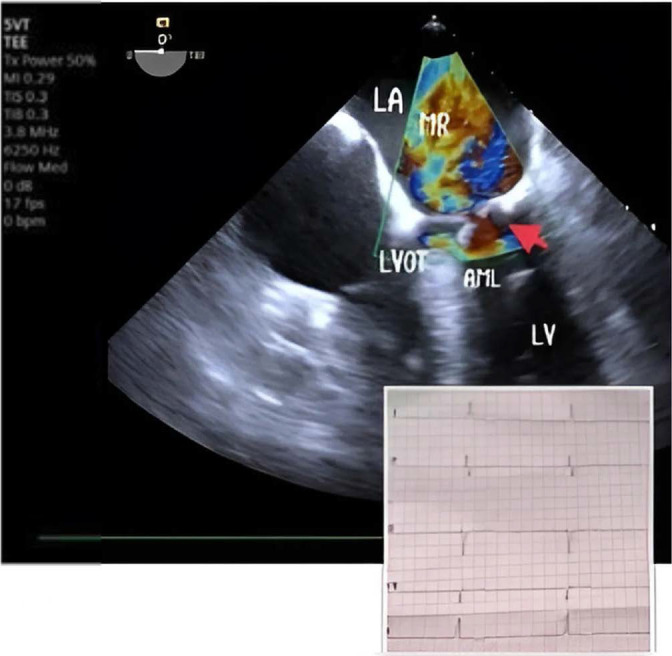

Systolic anterior motion (SAM) of the mitral valve refers to the unusual movement of the anterior and sometimes the posterior mitral valve leaflets toward the left ventricular outflow tract (LVOT) during systole. This phenomenon is most frequently associated with the asymmetric septal variant of hypertrophic cardiomyopathy (HCM), but it can also occur in conditions like acute myocardial infarction, diabetes mellitus, hypertensive heart disease, after mitral valve repair, and even in asymptomatic individuals during dobutamine stress tests. We present a case of transient SAM induced by a junctional rhythm along with high doses of dobutamine and nitroglycerin in an intensive care unit (ICU) setting. Transesophageal echocardiography (TEE) played a crucial role in detecting SAM and showed that transitioning from a junctional rhythm to a ventricular paced rhythm led to an improvement in the SAM condition.

Abstract Image